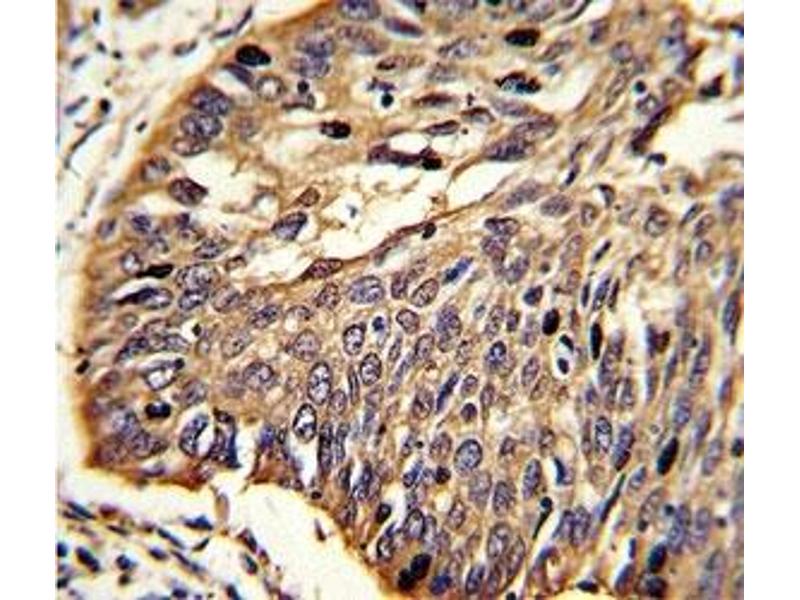

Titration of the MyD88 antibody may be required due to differences in protocols and secondary/substrate sensitivity.\. Western blot: 1:1000,IHC (Paraffin): 1:10-1:50,Flow Cytometry: 1:10-1:50